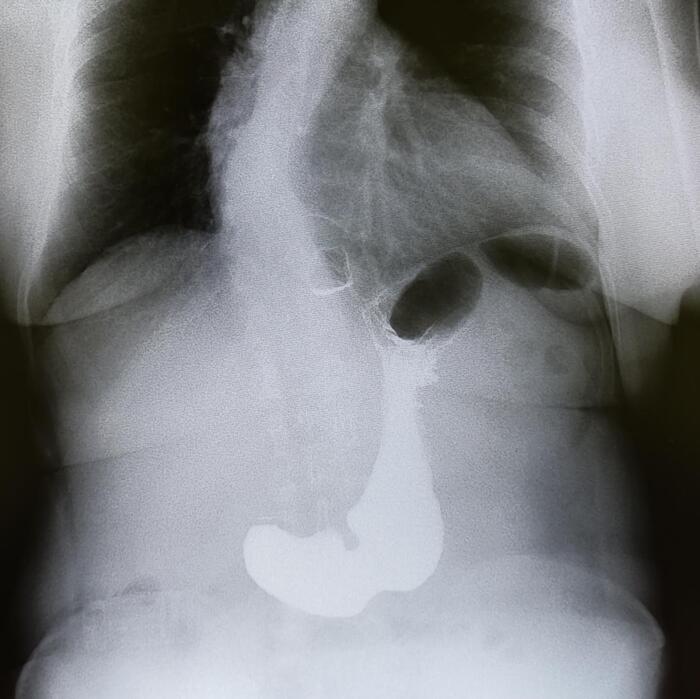

Эностоз может встречаться в любой кости, но чаще всего обнаруживается в губчатом веществе костей (например, в позвонках, тазовых костях, ребрах, длинных трубчатых костях).

Варианты эностозов на КТ И МРТ.